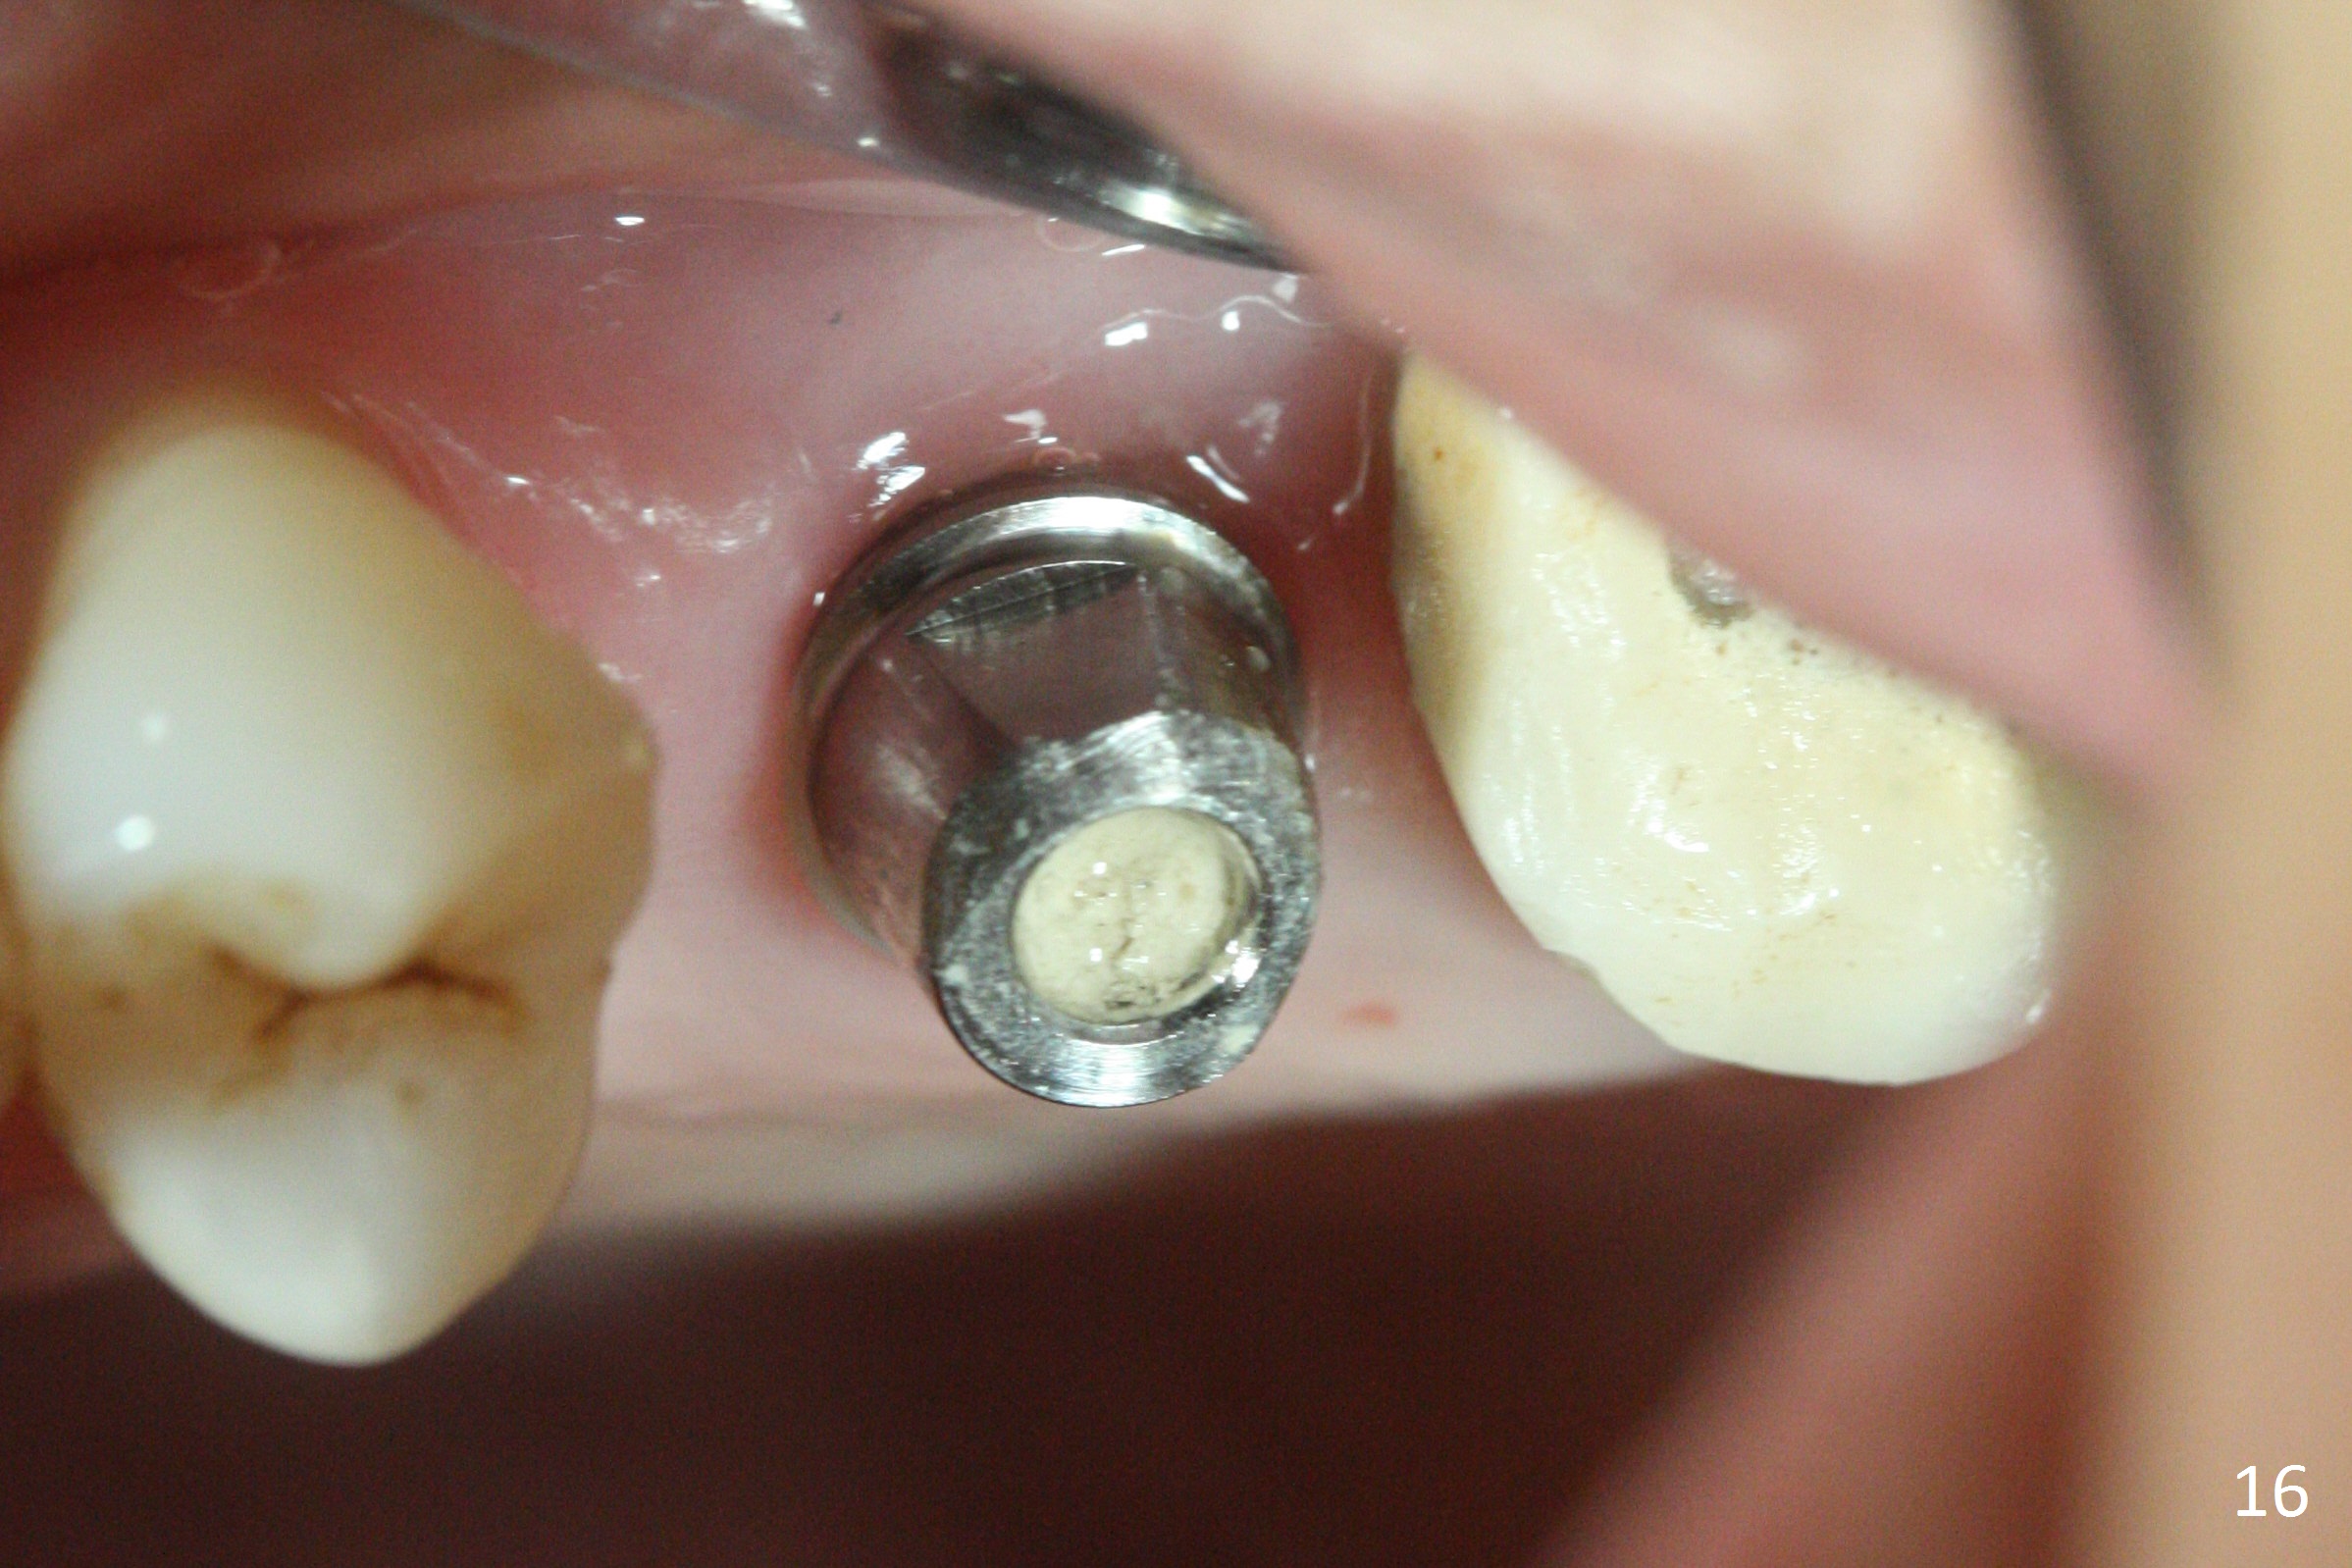

The implant is stable 8 months postop (Fig.15). When a 6x4(3) mm abutment is placed 8.5 months postop, it is distal (Fig.16). The mesiodistal width is 1-2 mm shorter than that at #3, which suggests the mesial shift of the tooth #15. A provisional is fabricated at #14 (Fig.17 P) with supra-occlusion so that there is clearance between the tooth #15 and the opposing one (Fig.18 *). With a separator placed between #14 and 15 (Fig.19), the latter is free to be distalized. Bone volume and density seem to increase 4.5 and 10.5 months post cementation (Fig.20,21, as compared to Fig.15), although the buccal plate remains as concave as shown in Fig.18. One year 5 months post cementation, the patient complains of bad smell from the implant when water pik is being used. It appears that the 1st 2-3 threads are exposed (Fig.22), although the surrounding gingiva remains uninfected. Bone graft is recommended. The site heals without bad smell 7 months post bone graft (2 years 4 months post cementation, Fig.23). The 1st implant thread is found exposed buccal on uncover (regraft?). A small healing abutment is placed because the implant is placed distal (Fig.24). An angled abutment should be tried and #15 crown will be redone. Impression will be taken when the gingiva heals around the provisional crowns.